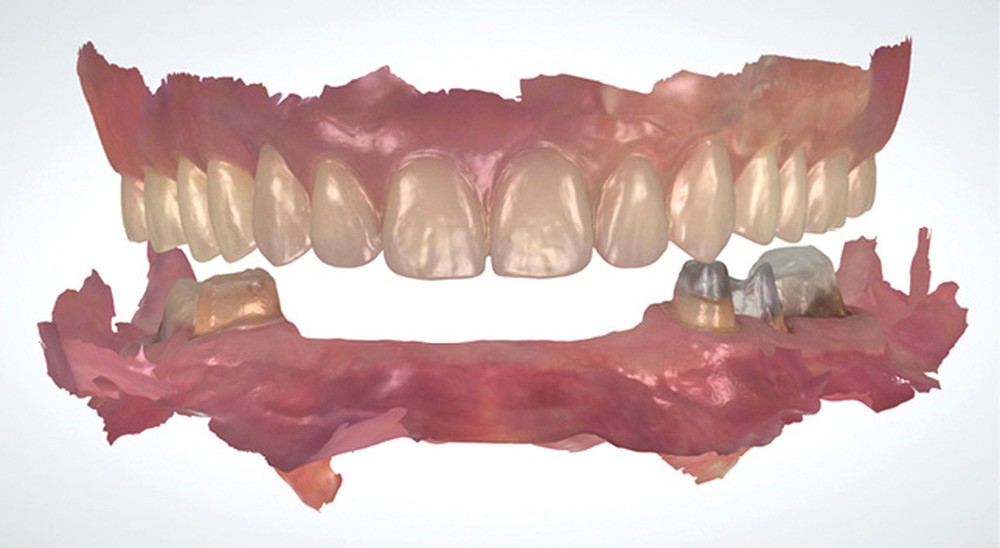

L’empreinte optique permet de positionner des points dans l’espace et l’ensemble de ses points crée le fichier 3D de l’empreinte. Ce référencement offre la possibilité d’enregistrer les arcades sans mordus ou cire d’occlusion dans les cas où le calage postérieur est absent (fig. 1).

La corrélation de fichiers est un vrai facilitateur pour les plans de traitement prothétique ; que ce soit pour le suivi des cas, ou dans des cas particuliers comme celui de la couronne sous châssis. Cette situation est toujours préjudiciable pour le patient en empreinte conventionnelle, car elle oblige à priver ce dernier de sa prothèse adjointe le temps que le laboratoire conçoive la couronne. Avec l’empreinte optique, il suffit d’enregistrer le crochet et sa position par rapport à la préparation pour que le prothésiste puisse concevoir une prothèse adaptée à la cavité buccale et à la prothèse amovible. Autre cas particulier, lors de la réalisation d’inlay-core, les logiciels de laboratoire ont des algorithmes qui autorisent la conception en seul temps de l’inlay-core et de la couronne avec un calcul des morphologies des éléments pour qu’ils respectent à la fois l’homothétie et les épaisseurs minimales de matériau (fig. 3 et 4).